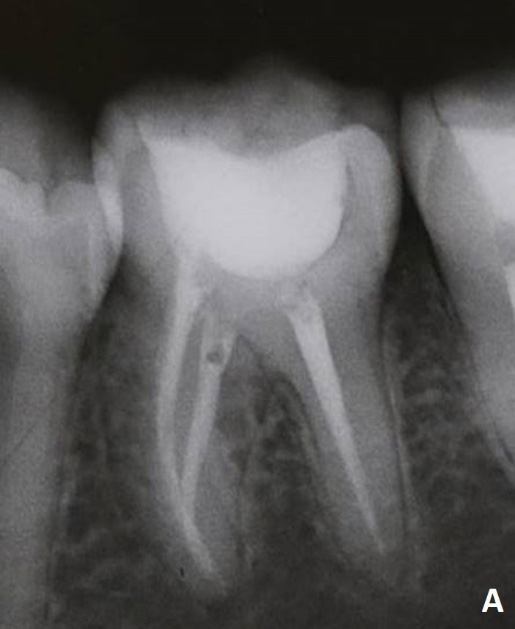

At the last appointment, the tooth showed a reduction in the periapical lesion in the mesial root on radiographic examination, and the patient was symptom-free. The filling was performed using the lateral and vertical condensation technique with MTA-based cement (MTA Fillapex Automistura, Angelus Indústria de Produtos Odontológicos S/A) and gutta-percha cones.

Final radiographic appearance